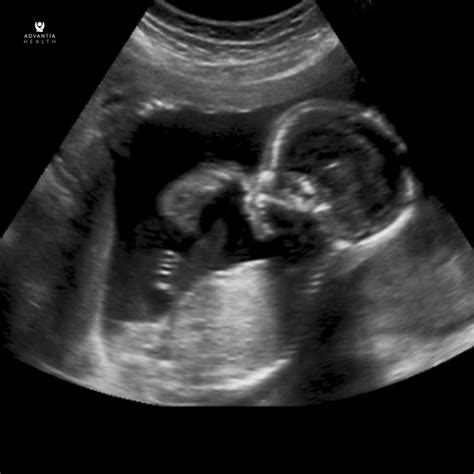

Reaching the midpoint of your pregnancy is a monumental milestone that brings a mix of excitement, nerves, and anticipation. Among the many prenatal appointments on your calendar, the anatomical scan at 20 weeks stands out as one of the most critical. Often referred to as the "mid-pregnancy ultrasound" or the "anomaly scan," this diagnostic procedure provides a comprehensive look at your developing baby’s physical structure and overall health. It is a moment where the abstract feeling of pregnancy becomes startlingly real as you get to see your baby's features, movements, and heartbeat in vivid detail on the screen.

The anatomical scan at 20 weeks is strategically timed. At this stage, the baby is large enough for the internal structures to be clearly visualized, yet small enough to move around relatively easily within the womb. Waiting much longer can make it difficult to get a complete view as the baby becomes more cramped, while earlier scans may lack the resolution needed to see delicate structures like heart valves or small vessels.

Beyond the Medical Data

While the clinical aspect of the anatomical scan at 20 weeks is the priority, many parents cherish this experience as a bonding moment. You may be able to see your baby sucking their thumb, yawning, or kicking. Some facilities provide photos or digital files of these images. Remember to discuss your expectations with your partner and your healthcare provider beforehand regarding how you wish to handle the revelation of the baby's sex or other findings.